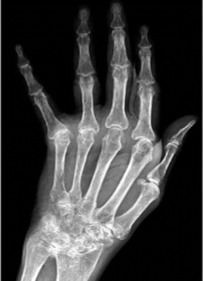

Rheumatoid Arthritis

Late dislocations

Ulnar deviation

Rheumatoid Arthritis joint contractures & deformities

Ulnar deviation of the fingers

Radial deviation of wrist

Swan-neck, Boutonniere deformities of the fingers